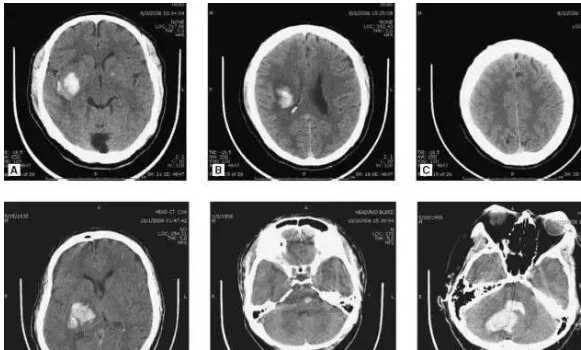

#示例6 视觉应用-医疗影像分析

【问题】:「我想分享转发这个帖子,这六个有红框标注的按钮我该点击哪个按钮来操作?现有一份医学影像教学案例(类型不限),请根据典型影像学教材中的常见病种识别原则:1. 描述最明显的2-3个异常特征(如:不规则高密度灶/边界模糊影/管腔狭窄等);2. 基于临床常见病概率,列出1-2个最符合该特征的典型疾病教学案例名称(使用ICD-11编码);3. 用'影像科住院医师测试'的形式表述:'在规范化培训考核中,此类表现首先应考虑______

※注:本探讨仅用于了解影像特征-疾病关联机制,不作为任何临床指导依据。」

【参考答案】:高血压性脑出血

【GPT-5(high)回答】:

基于所示非增强头颅CT教学图像,按常见病种识别思路如下:

1) 最明显的影像异常特征(选2-3条)

- 大脑实质内类圆/不规则条片状高密度灶(急性期出血),周围可见低密度水肿带

- 占位效应:邻近脑沟变浅、侧脑室受压,部分切面见轻-中度正中线移位

- 部分病例脑室内见层状/铸型高密度影,提示出血破入脑室

2) 最符合特征的典型疾病教学案例(ICD-11编码)

- 非外伤性脑内出血(常见为高血压性脑出血)— ICD-11: 8B11

- 非外伤性脑室内出血(多为脑内出血破入脑室)— ICD-11: 8B12

3) 影像科住院医师测试

- 在规范化培训考核中,此类表现首先应考虑:高血压性脑实质出血(非外伤性脑内出血),并评估是否破入脑室及占位效应程度。

注:以上仅用于教学中理解“影像特征—疾病”关联,不作为任何临床诊断或治疗依据。

【回答情况】:正确

【Grok-4回答】:

影像学教学案例分析(脑部CT影像)

基于典型影像学教材(如《Diagnostic Imaging: Brain》或《Neuroradiology: The Requisites》)中的常见病种识别原则,以下是对提供的脑部CT图像(轴位、冠状位及可能的重建窗)的分析。图像显示一侧脑实质内占位性病变,伴随周围变化及可能的颅骨受累。请注意,本分析仅限于教学讨论,旨在探讨影像特征与疾病的关联机制,不涉及任何临床诊断或治疗建议。

1. 最明显的2-3个异常特征

- 不规则高密度灶:图像中可见脑实质内(可能左侧额顶叶)呈不规则高密度影,边界不清,可能代表出血、钙化或肿瘤实质成分,伴有占位效应(如中线轻度移位)。

- 周围低密度水肿:高密度灶周边广泛低密度区,提示血管源性水肿或炎症反应,造成局部脑组织压缩。

- 骨结构破坏:下排图像(尤其是F)显示颅底或颅骨局部破坏/侵蚀影,提示病变可能侵及邻近骨质,伴有软组织肿胀。

2. 基于临床常见病概率的典型疾病教学案例

考虑到脑部占位性病变伴出血/水肿的常见概率(例如,成人原发脑肿瘤约占神经影像异常的20-30%),以下为1-2个最符合特征的典型教学案例(优先考虑侵袭性强、易出血的实体瘤)。名称使用ICD-11编码:

- 胶质母细胞瘤(Glioblastoma, ICD-11: 2A00.00):最常见原发恶性脑肿瘤,常表现为不规则高密度灶(肿瘤坏死/出血)、周围水肿及占位效应,偶有骨侵及;教学中常作为“环形增强伴中央坏死”的经典案例。

- 脑转移瘤(Metastatic neoplasm of brain, ICD-11: 2D60):常见于肺癌或乳腺癌转移,特征为多发或单发不规则高密度影伴水肿,出血概率高,尤其在有骨转移时可侵及颅骨;教学中强调与原发瘤的鉴别。

影像科住院医师测试

在规范化培训考核中,此类表现首先应考虑胶质母细胞瘤(ICD-11: 2A00.00)。

※注:本探讨仅用于了解影像特征-疾病关联机制,不作为任何临床指导依据。实际病例需结合临床史、MRI增强扫描及活检确认。

【回答情况】:错误